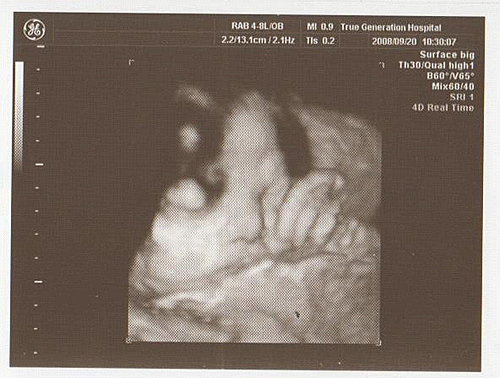

照超音波時

頭圍和腹圍都符合週數

但大腿骨大約是33週多的長度

可是侯醫師也沒有說什麼

胎兒心臟正常

胎盤也正常

沒有臍繞頸

寶寶的體重大約2455公克

預計出生時約3000~3200公克